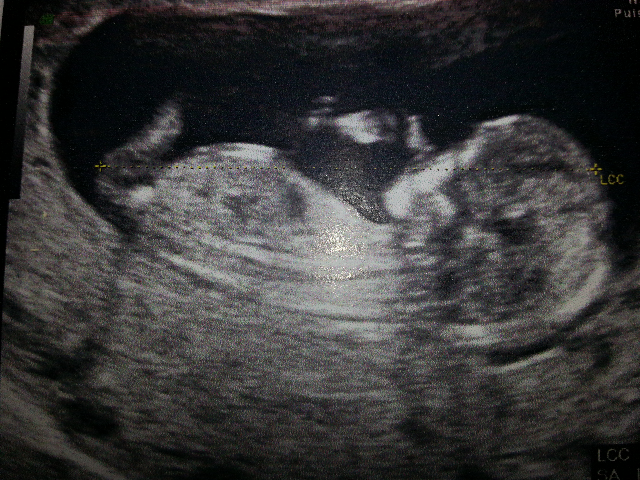

En fait ce que tu as vu Rélie c'est le bourgeon génital! il est le même chez les filles et chez les garçons à ce stade c'est uniquement l'inclinaison par rapport au dos qui permet de dire si c'est un petit mec ou une petite fille... c'est pour ca que certains ne se prononcent pas de suite car des fois le bourgeon n'est pas encore monté par exemple. Mais y a plus de risques d'erreur dans le cas de l'annonce d'une petite fille. Une copine sage femme m'a tout expliqué et elle, ne se prononce pas à cause des risques mais si on t'a dit garçon y a moins d'erreur.Vous pensez que je dois le dire a ma mère et ma belle mère? En fait du coup je flippe un peu lool elle la vu les jambes en l'air donc fesses et sexe juste sous nos yeux et je me dis que si elle été pas sûre elle me l'aurai pas dit non?

Sur cette photo tu vois bien la différence